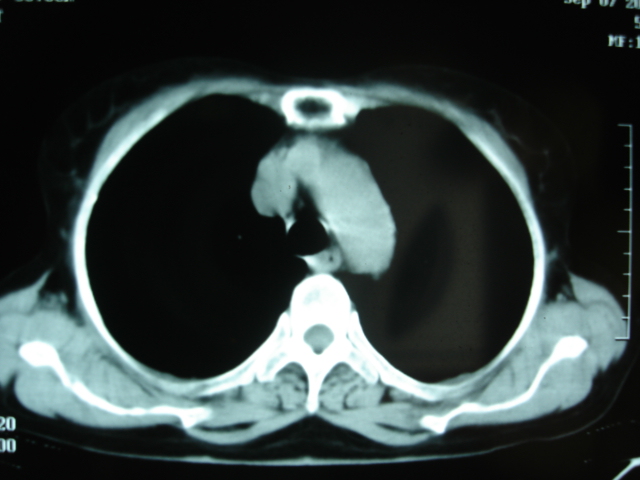

以下是引用卜一在2009-9-7 19:51:00的发言:[br][br] 1 左侧胸内甲状腺占位-多考虑甲状腺腺瘤! 2、左肺门占位-建议增强扫描以便明确性质。 3 慢支并感染! [br]

以下是引用shibing在2009-9-7 20:40:00的发言:[br]左侧胸内甲状腺占位-多考虑甲状腺腺瘤! 2、左肺门占位-建议增强扫描以便明确性质。 3 慢支并感染! [br]